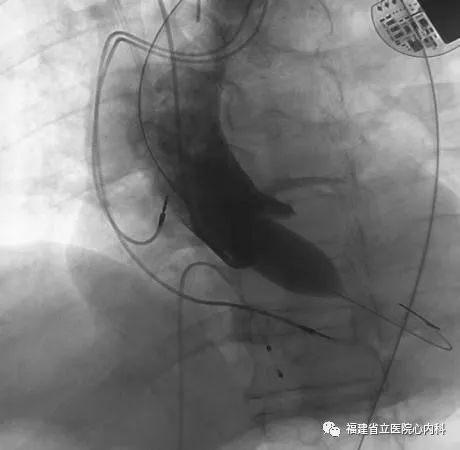

病例2

该病例是TYPE0型二叶瓣,瓣叶增厚伴极重度钙化,同时升主动脉增宽且为横位心,导致输送系统通过主动脉弓及瓣膜口难度明显增加,而且瓣上存在限制结构,瓣膜移位风险高,术中手术团队默契配合,输送系统顺利通过主动脉弓及狭窄的瓣口,Venus A-L26瓣膜定位精准释放,达到术前预期锚定位置,最终效果佳。

瓣环

窦部

球囊预扩张

植入L26瓣膜